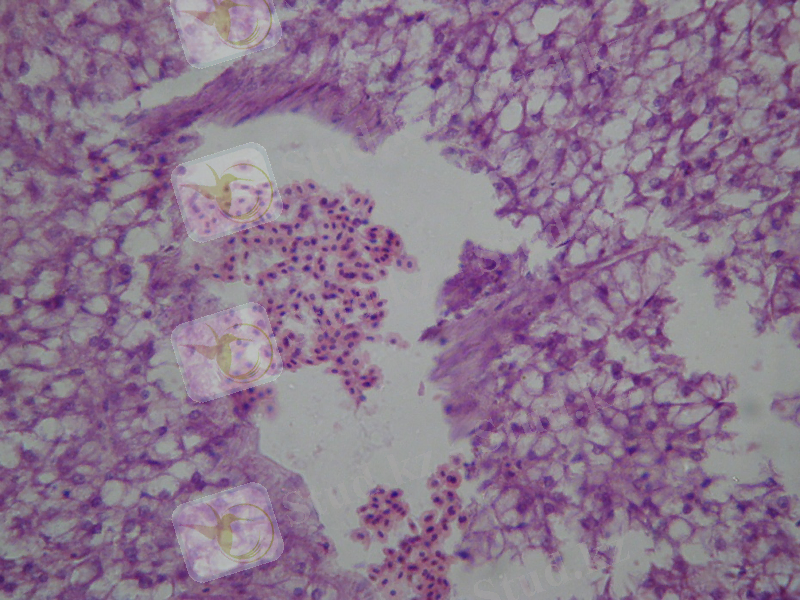

Бұл ауданнан алынған балықтардың бауырында кейбір патологиялық өзгерістер байқалады. Ол өзгерістер ірі және кіші қан тамырларының тамыр қабырғасының бұзылуы, қан стазы, қабырға тромбтарының пайда болуы, периваскулярлы ісіну (2-сурет) .

2-сурет. Бірінші аудан. Бұзаубас балық бауыры. Қабырға тромбы пайда болған қан стазы. Периваскулярлы ісіну. Некроз ошақтары. Гематоксилин-эозинмен бояу. 400 есе үлкейту.

Купфер клеткасының пролиферацияланған участкілерінің пайда болуы байқалады (3-сурет) . Пролиферация - зақымдалған бауыр клеткаларының митоз жолымен бөлініп, қайта қалпына келуі.

3-сурет. Бірінші аудан. Бұзаубас балық бауыры. Периваскулярлы ісіну. Купфер клеткаларының пролиферациясы. Некроз ошақтары. Гематоксилин-эозинмен бояу. 400 есе үлкейту.